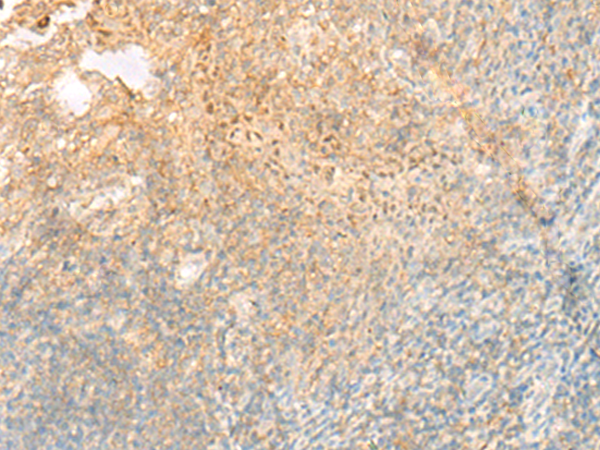

分类: 科研抗体货号: P13509别名: PSP24B; PSP24(beta)应用: IHC反应种属: Human, Mouse